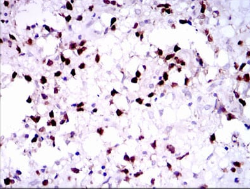

PAX5 Mouse Monoclonal antibody[7D3D8]

IHC    1/200 - 1/1000